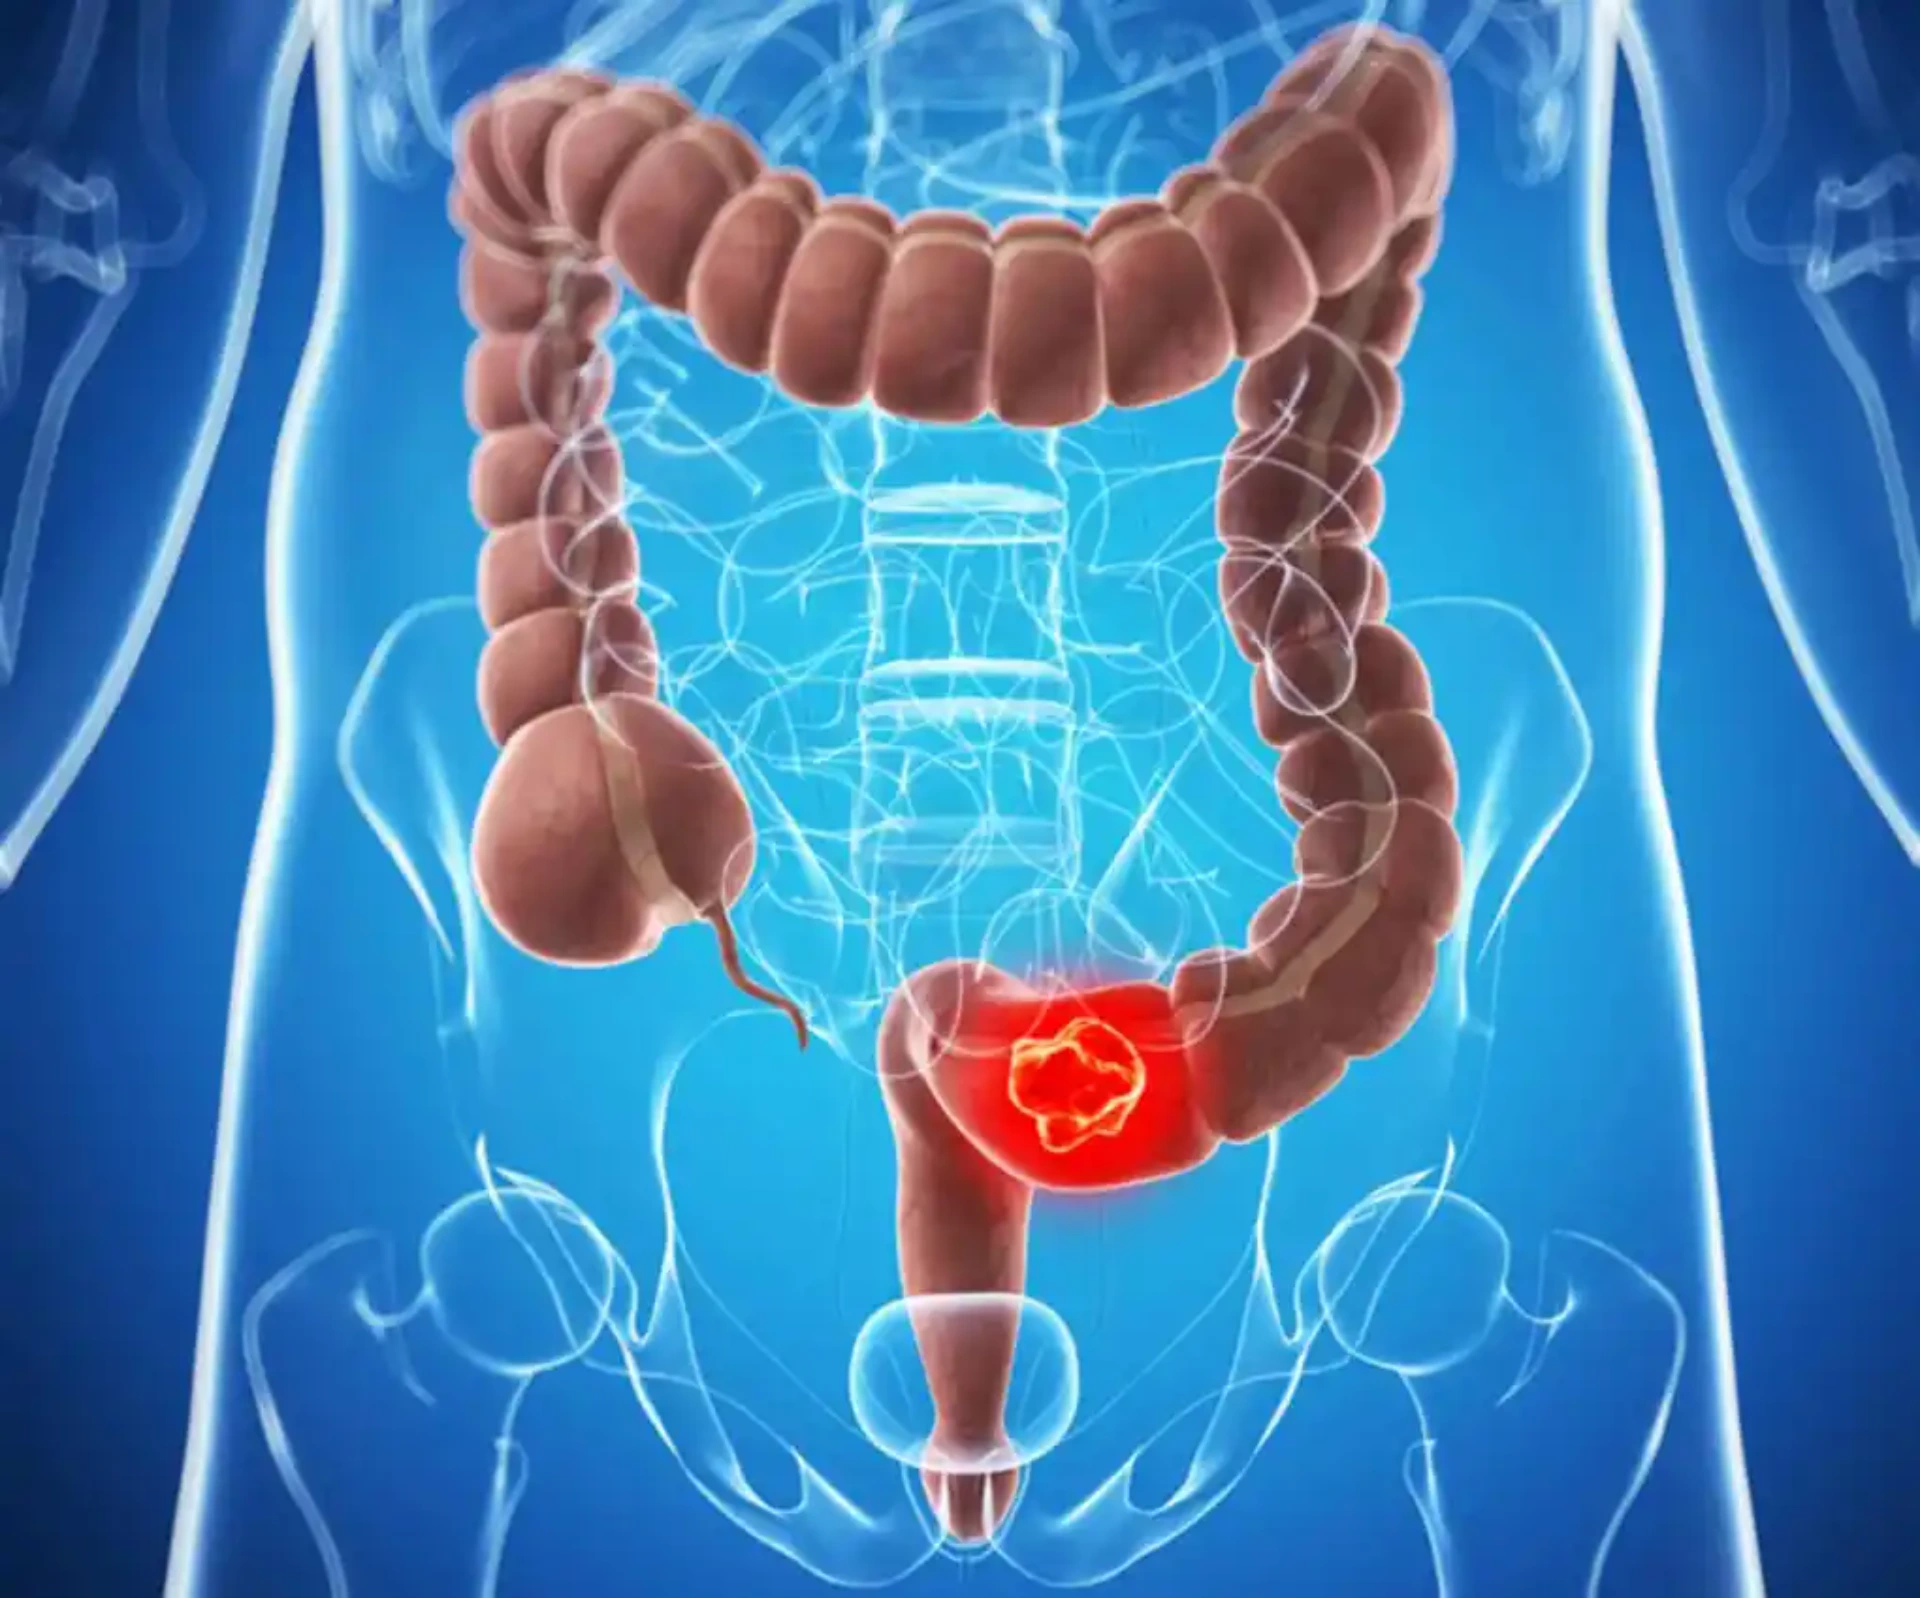

Kolon xərçənginin əsas səbəbləri arasında genetik amillər, qeyri-sağlam qidalanma alışkanlıqları, aş ...